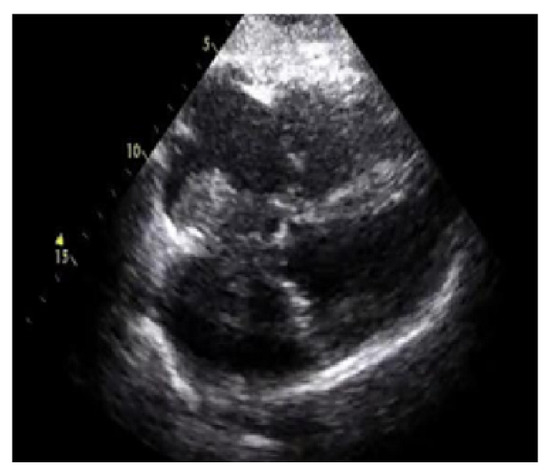

IoT-Enabled Classification of Echocardiogram Images for Cardiovascular Disease Risk Prediction with Pre-Trained Recurrent Convolutional Neural Networks

Cardiovascular diseases currently present a key health concern, contributing to an increase in death rates worldwide. In this phase of increasing mortality rates, healthcare represents a major field of research, and the knowledge acquired from this a...